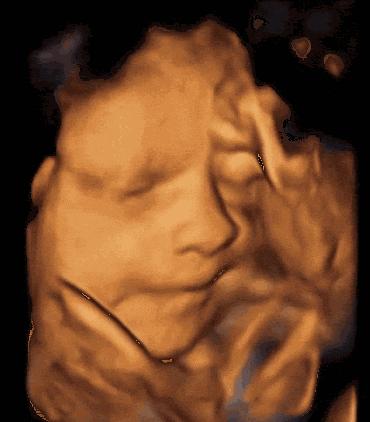

我想这些疑问,很多妈妈在孕期也有过,下面用8组图告诉你,胎儿在妈妈的肚子里,除了睡觉,还会干些啥?动作多到你意想不到。

宝宝在娘胎里有8项活动,生活很丰富多彩

其实,胎宝宝在娘胎里做的事情,远不止这些,还有可能做鬼脸、皱眉、张嘴舔胎盘、咂摸嘴巴尝羊水味道等有趣的事情。看到这些,你是否也觉得很神奇呢?